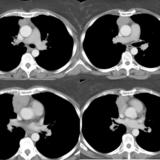

Case 9 Thymoma CT

Date: 04/04/2010

Views: 3590